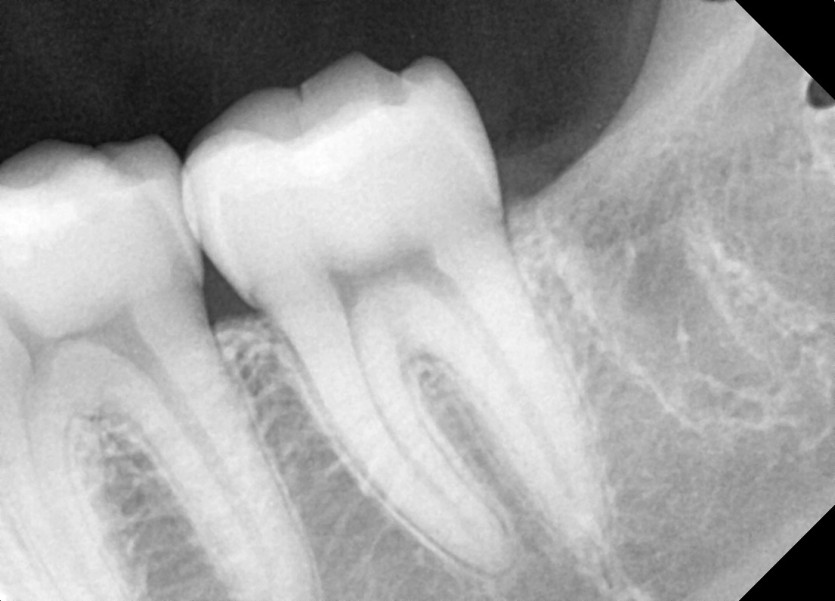

#28,38 사랑니 발치

구강 외과 전문의가 당일 발치했습니다.